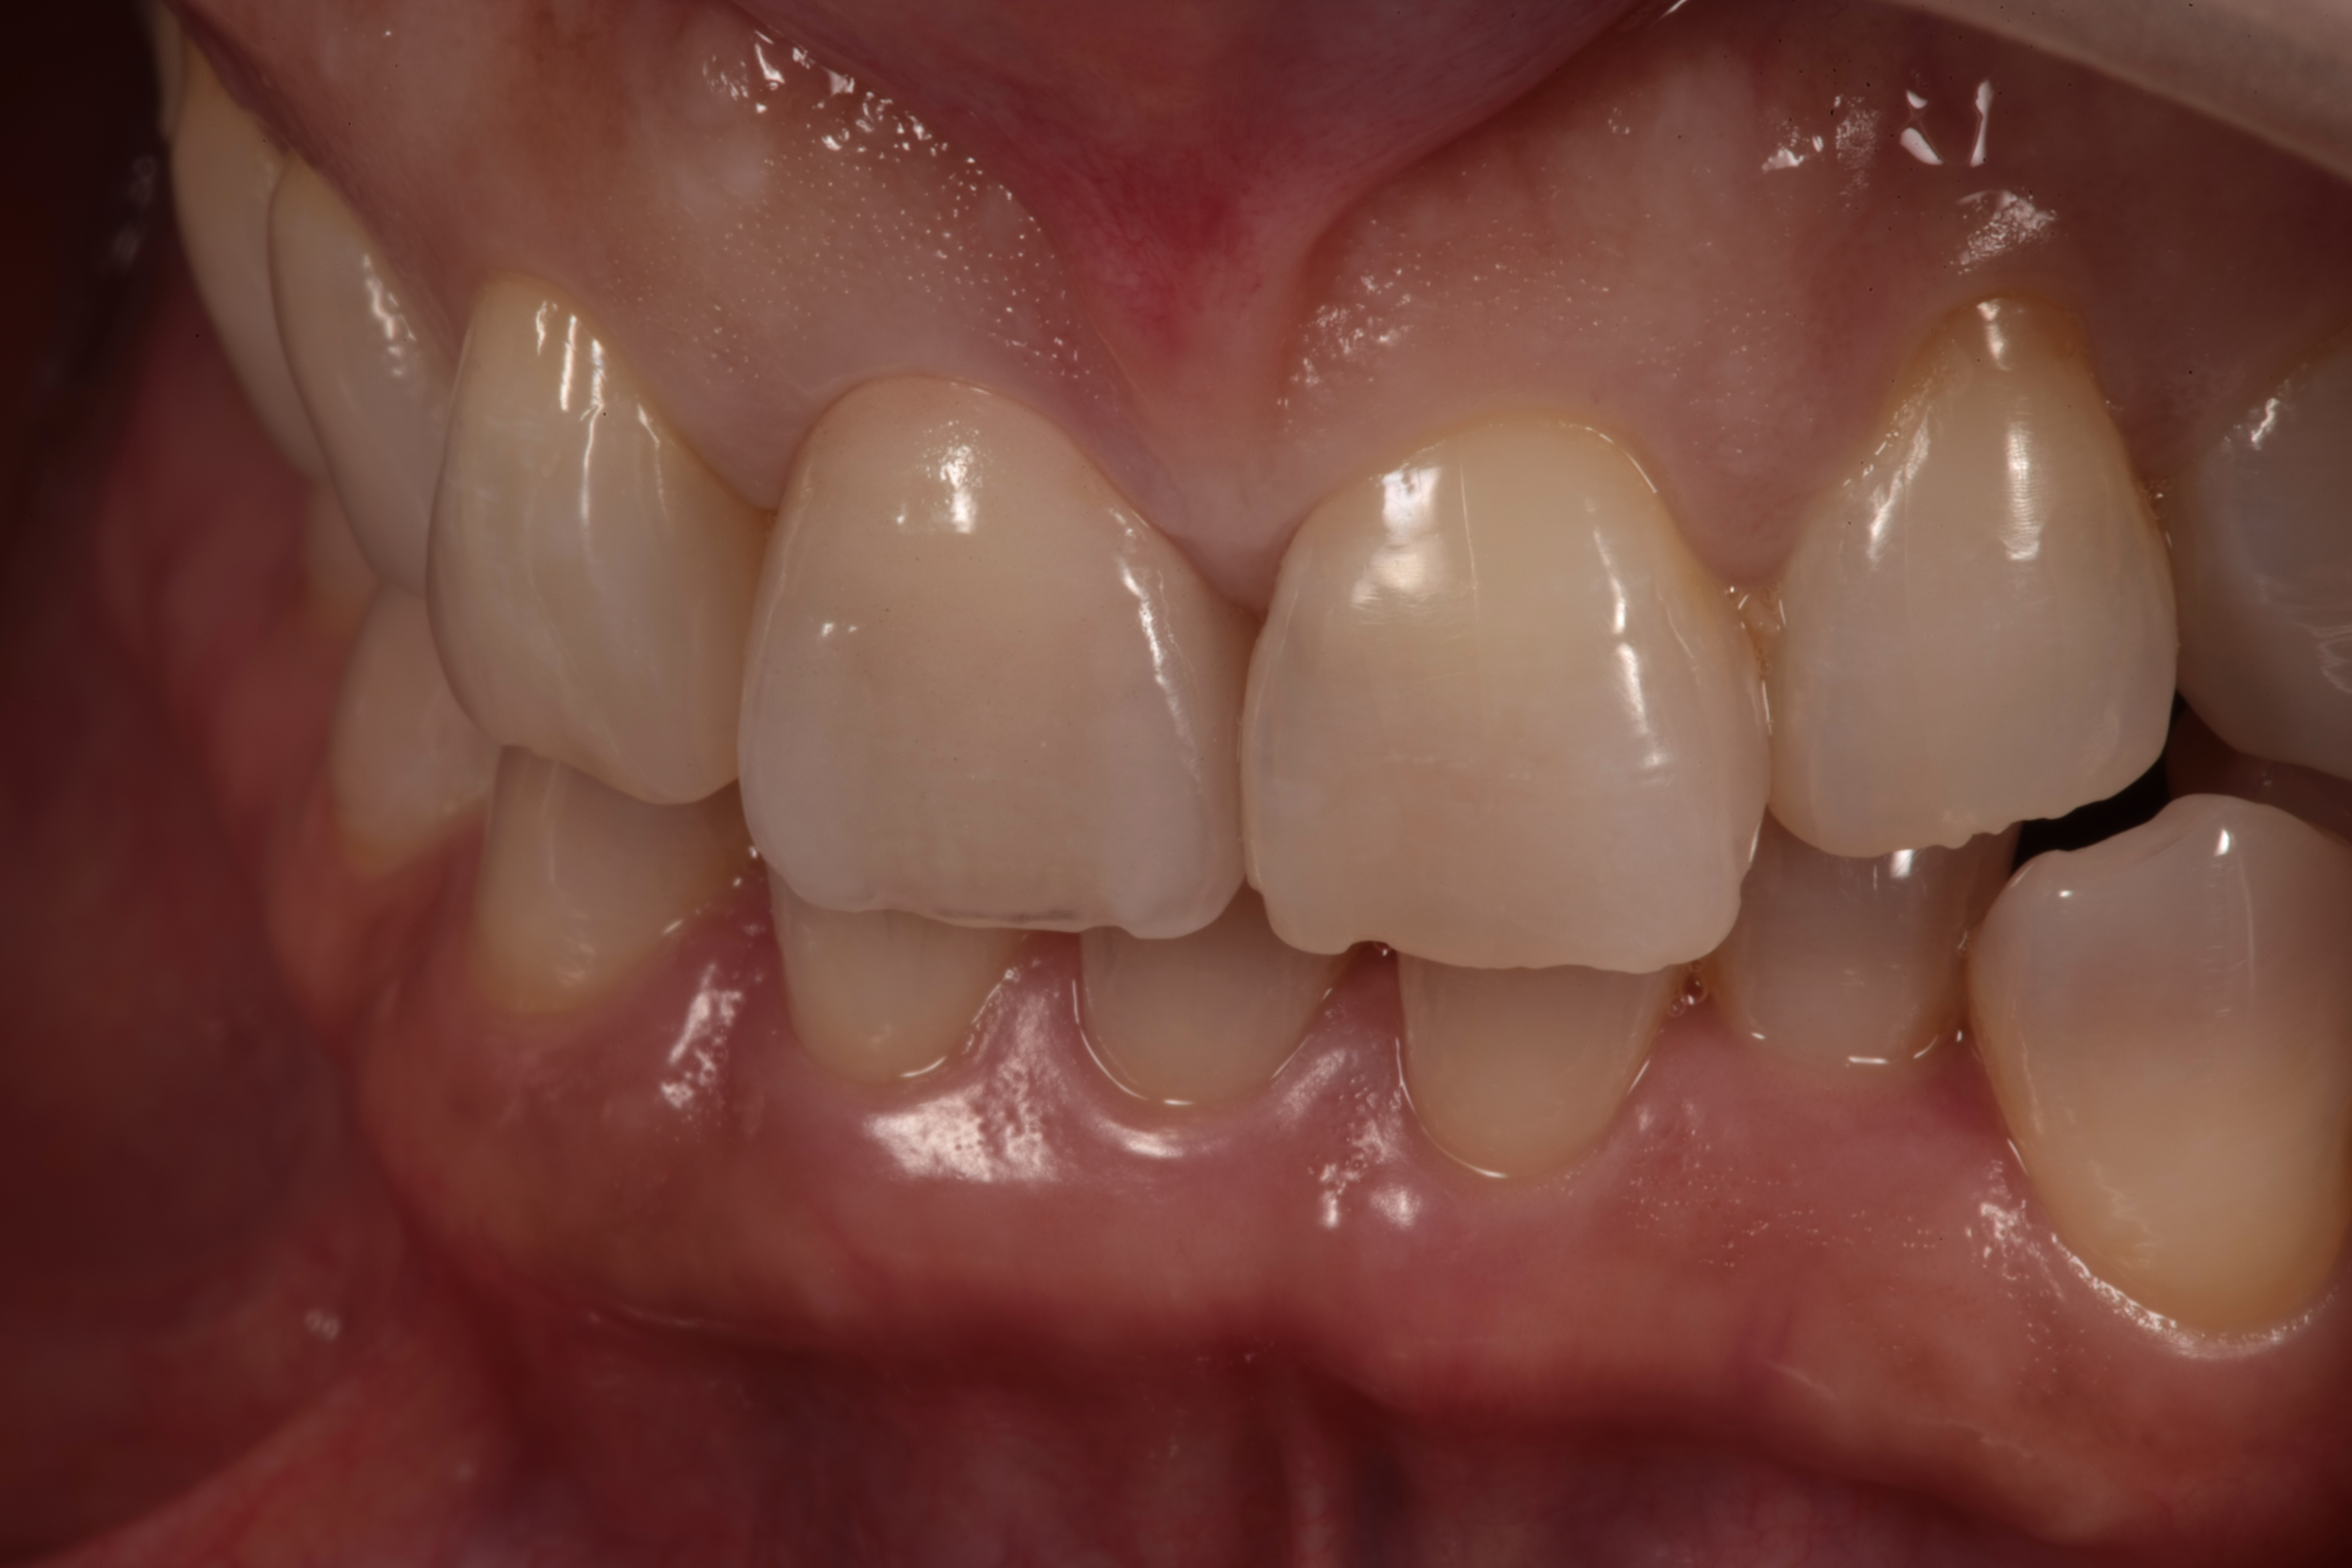

最終的な歯が仕上がった状態です(*^-^*)

どこを治療したか分からない仕上がりですね!

綺麗にセラミックの歯が入っています。

横から見ても自然な色に仕上がっています。

左右のバランス、下の歯とのバランス、

そして細かい形が再現されています。

口元が自然な仕上がりですね(^^)